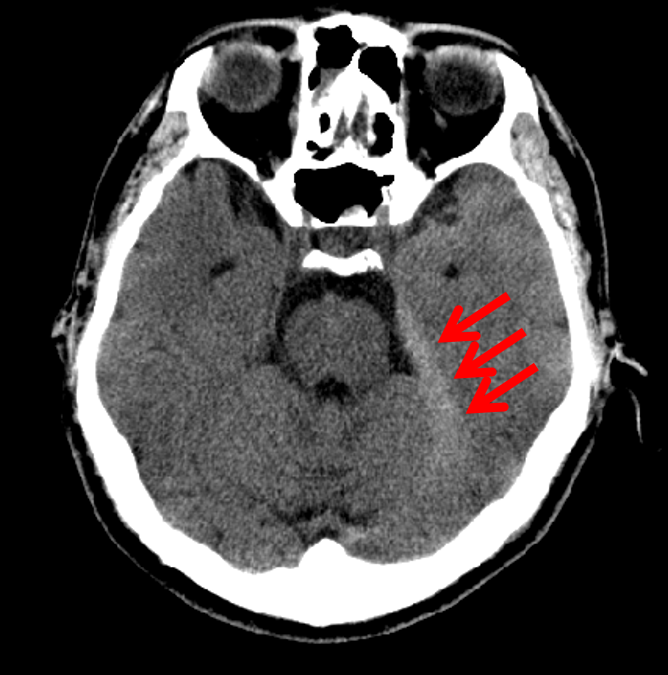

Figure 11: BCT most likely to have an abnormality according to the logarithm posterior probability out of the 33 abnormal BCTs used for testing (subdural hematoma along the left cerebellar tentorium).

Refer to caption

Figure 12: BCT most likely to have an abnormality according to the logarithm posterior probability out of the 33 abnormal BCTs used for testing. This is an enlarged version of a part of Fig. 11, and the lesion is pointed out with red arrows.

Figure 13: BCT second most likely to have an abnormality according to the logarithm posterior probability out of the 33 abnormal BCTs used for testing (acute infarction in the left posterior cerebral artery territory).

Figure 14: BCT second most likely to have an abnormality according to the logarithm posterior probability out of the 33 abnormal BCTs used for testing. This is an enlarged version of a part of Fig. 13, and the lesion is pointed out with red arrows.

Figures 11 and 12 show the BCT most likely to have an abnormality according to the logarithm posterior probability out of the 33 abnormal BCTs used for testing. Figures 13 and 14 show the BCT second most likely to have an abnormality according to the logarithm posterior probability out of the 33 abnormal BCTs used for testing.